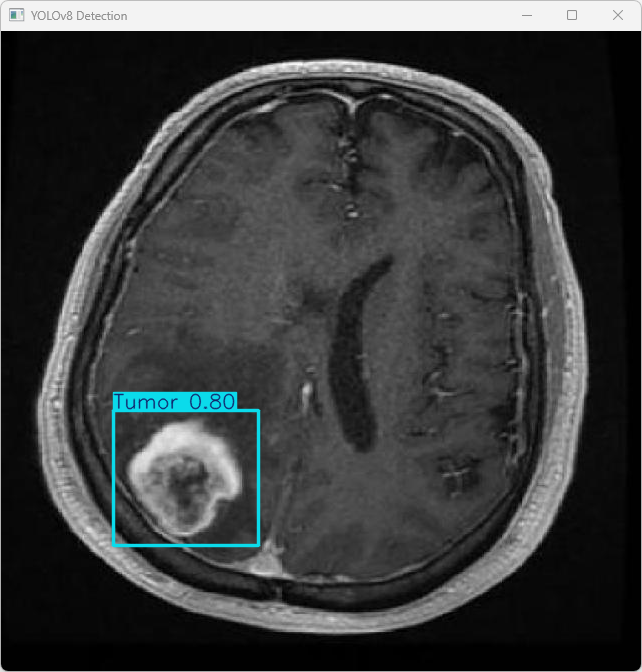

4.检测结果识别

模型训练完成后,我们可以得到一个最佳的训练结果模型best.pt文件,在runs/train/weights目录下。我们可以使用该文件进行后续的推理检测。

imgTest.py 图片检测代码如下:

执行imgTest.py代码后,会将执行的结果直接标注在图片上,结果如下:

这段输出是基于YOLOv8模型对图片“imagetest.jpg”进行检测的结果,具体内容如下:

图像信息:

(1)处理的图像路径为:TestFiles/imagetest.jpg。

(2)图像尺寸为640×640像素。

检测结果:

(1)模型在图片中检测到:1 个肿瘤 (Tumor)。

处理速度:

(1)预处理时间: 6.1 毫秒

(2)推理时间: 5.0 毫秒

(3)后处理时间: 102.6 毫秒

YOLOv8模型医学影像脑肿瘤检测系统已经具备良好的检测能力,可以进一步用于实际应用场景。